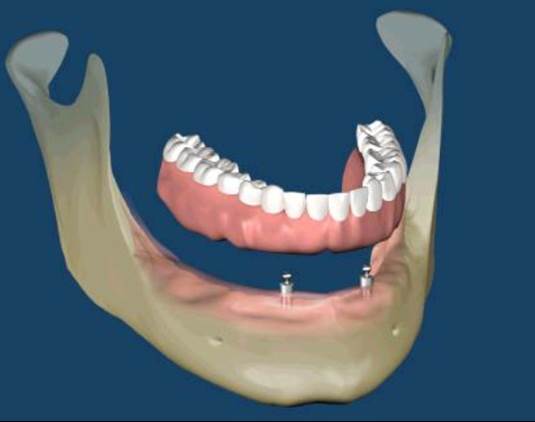

All-on-Fou/Six

近年來由於人工植牙的技術普及,患者大都知道植牙可做固定式假牙,但同樣的有時患者因為身體、經劑因素等受限,也可以考慮植入幾支人工植牙,再完成固定可撤式活動義齒,這樣可讓活動式假牙的固定性有效加強。通常上顎可用6支植體,下顎則4-5支植體固定,如需更穩定的受力,亦可再增加植體數目。(圖52-55)